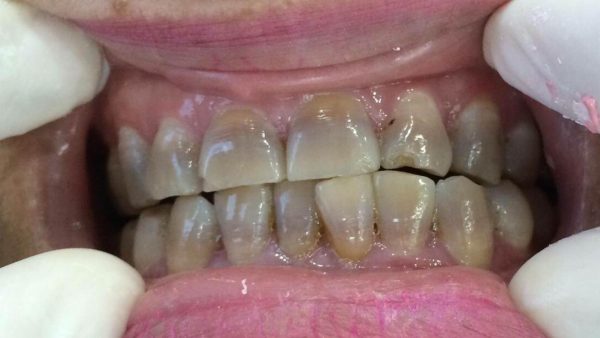

Tuy nhiên, một số người khi trưởng thành răng sẽ có màu vàng xám, vàng đen hoặc xám đen – đây chính là tình trạng răng bị nhiễm màu kháng sinh. Răng nhiễm kháng sinh hay gọi một cách đầy đủ là răng nhiễm kháng sinh Tetracycline (Tetra).

Tình trạng răng bị nhiễm màu kháng sinh sẽ có sự khác nhau ở từng người. Cấp độ nhiễm màu còn phụ thuộc vào thời điểm dùng thuốc, liều lượng dung nạp và cơ địa của từng người. Sự khác nhau này biểu hiện ở những dải màu khác nhau trên răng, cụ thể như sau:

➤ Cấp độ 1: Màu răng vàng xám

Đây là cấp độ thấp nhất của màu kháng sinh, nếu nhìn sơ qua bạn có thể nghĩ rằng răng mình chỉ là ố vàng do thực phẩm nhưng nếu quan sát kỹ hơn thì sẽ thấy những vệt màu xám nhạt ở giữa thân răng hoặc chân răng.

➤ Cấp độ 2: Màu vàng đen

Ở cấp độ này, bạn có thể dễ dàng quan sát thấy những vệt vàng và đen đan xen rõ rệt ở thân răng và chân răng.

➤ Cấp độ 3: Màu xám đen

Lúc này, màu vàng ngà đã mất hoàn toàn, răng bạn nhìn như một chiếc răng đã chết tủy với màu xám đen bao trùm toàn bộ thân răng. Đáng nói hơn, răng bạn còn có thể xuất hiện tình trạng bị lỗ chỗ và hình thể răng bị biến đổi. Ở cấp độ này, răng sẽ đối mặt với rất nhiều nguy cơ bệnh lý răng miệng nguy hiểm do men răng đã bị tổn thương.